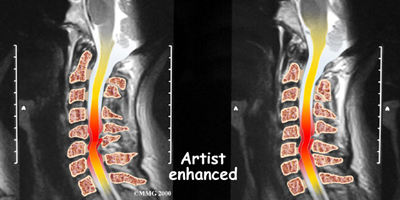

If more information is needed, your doctor may order an MRI. The MRI machine uses magnetic waves rather than x-rays to create pictures of the cervical spine in slices. MRIs show the cervical spine vertebrae, as well as the soft tissue structures, such as the discs, joints, and nerves. MRI scans are painless and don't require needles or dye. MRI scan has become the most common test to look at the cervical spine after x-rays have been taken.

When the head and neck are suddenly and forcefully whipped forward and back, mechanical forces place excessive stress on the cervical spine. Traumatic disc rupture and soft tissue damage can occur. The cartilage between the disc and the vertebral bone is often cracked. This is known as a rim lesion.

Damage to the disc can put pressure on the nerves as they exit the spine. The pressure or irritation can be felt as numbness on the skin, weakness in the muscles, or pain along the path of the nerve. Most people think of these symptoms as indications of a pinched nerve. Health care providers call this condition cervical radiculopathy.